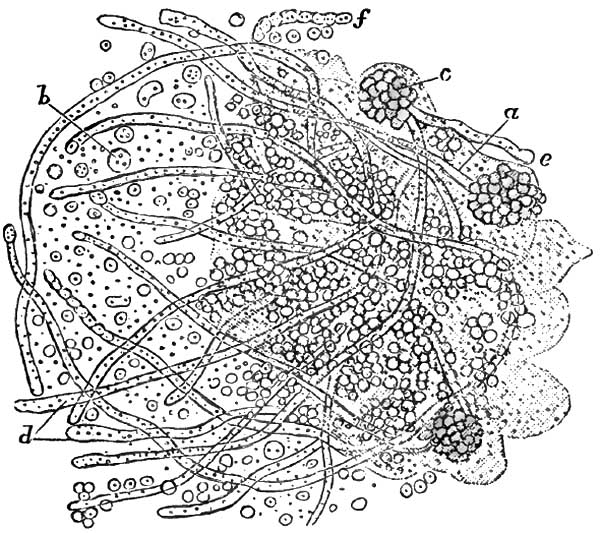

| 14. | CHRONIC INTUMESCENCE OF THE TONGUE (HARRIS) |